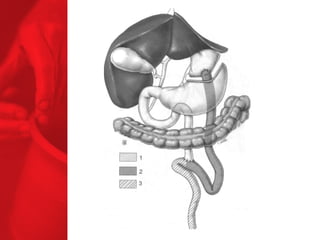

LA DIVERSION BILIO-PANCREATIQUE(DBP) Procédure de malabsorption Poche de l'estomac plus grande Plus grande perte de poids Plus grande malabsorption des nutriments Perte de surcharge pondérale de 74% la première année, 78% la deuxième année, 81% la troisième année, 84% la quatrième année et 91% la cinquième année*. diminue le diabète de type 2 chez près de 77% des patients** *Duodenal Switch: An Effective Therapy for Morbid Obesity – Intermediate Results” Baltasar A, Bou R. Obesity Surgery 2001 Feb; 11(1): 54-8. ** Buchwald H, Avidor Y, Braunwald E, et al. Bariatric Surgery—A Systematic Review of the Literature and Meta-analysis. Journal of the American Medical Association 2004 Oct 13;292(14).

COMMENT FONCTIONNE LADBP ? Facteurs chirurgicaux Restriction du volume des repas Malabsorption élevée Facteurs pour les patients Apport en calories Dépense en calories BILAN ENERGETIQUE = apport alimentaire dépense en énergie

DIVERSION BILIO-PANCREATIQUE (DBP)AVEC «SWITCH DUODENAL» Procédure de malabsorption Poche de l'estomac plus grande Plus grande perte de poids Plus grande malabsorption des nutriments Perte de surcharge pondérale de 74% la première année, 78% la deuxième année, 81% la troisième année, 84% la quatrième année et 91% la cinquième année*. Diminue le diabète de type 2 chez près de 77% des patients** *Duodenal Switch: An Effective Therapy for Morbid Obesity – Intermediate Results” Baltasar A, Bou R. Obesity Surgery 2001 Feb; 11(1): 54-8. ** Buchwald H, Avidor Y, Braunwald E, et al. Bariatric Surgery—A Systematic Review of the Literature and Meta-analysis. Journal of the American Medical Association 2004 Oct 13;292(14).

COMMENT FONCTIONNE LADBP AVEC LE SWITCH DUODENAL ? Facteurs chirurgicaux Restriction du volume des repas Malabsorption élevée Facteurs pour les patients Apport en calories Dépense en calories BILAN ENERGETIQUE = apport alimentaire dépense en énergie